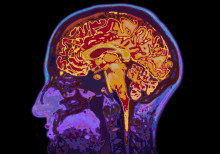

BRAIN COOLING STUDY

Brain injury treatment may cause harm in low and middle income nations

A procedure widely used to treat birth-related brain damage in new born babies in low and middle income countries (LMICs) may increase risk of death.